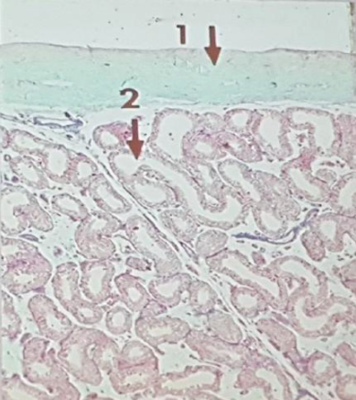

D'après les coupes que le prof présente dans son cours sur l'AGM il y a une chose que je ne saisi pas; les doubles flèches définissent un lobule ok, et chaque lobule possède en sa partie centrale un tube droit qui a pour rôle de drainer 5 à 6 TS. Donc chaque lobule ne contient que quelques TS, or les deux illustrations semblent autant l'une que l'autre montrer des lobules en possédant nombreux; est ce effectivement le cas et dans ce cas je veux bien une explication ou est ce que c'est simplement que l'on n'arrive pas bien à distinguer les cloisons des lobules sur ces coupes, ou encore est ce peut être d'autres structures que des TS ?